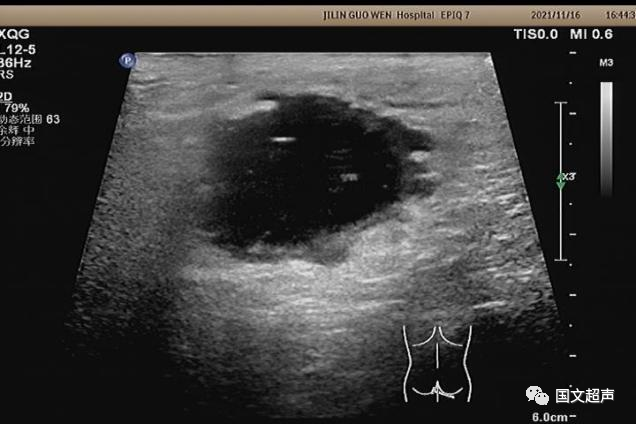

超聲檢查所見:

肛周:7點鐘方向皮下脂肪層內(nèi)探及不均質低無回聲包塊,范圍約4.6*3.0cm,較淺處距體表約0.6cm,邊界不清,周圍軟組織回聲增強,CDFI:周邊血流信號豐富,輕加壓探頭有涌動感,如下圖: